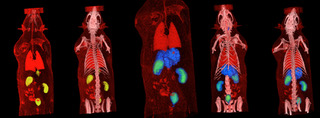

La técnica PET/CT para pequeños animales se basa en la inyección de un radiotrazador al que se le ha incorporado un isótopo emisor de positrones. En función de las características del trazador se acumulará de manera diferencial en los distintos compartimentos corporales. Su detección se basa en la emisión por parte del isótopo de un positrón que al encontrarse con un electrón vecino sufre un proceso de aniquilación. En dicho proceso se generan 2 rayos gamma de alta energía antiparalelos que son detectados por el anillo PET. Mediante un proceso posterior de reconstrucción se obtiene una imagen tridimensional la cual muestra la distribución del radiofármaco. Así, en el caso más común de usar 18F-FDG se obtiene un mapa de la actividad metabólica. Estos estudios pueden ser de utilidad en diversos campos: fisiología, farmacología, oncología, neurología, desarrollo de nuevos fármacos, modelos experimentales, etc. Todo ello se complementa con la información estructural recogida por el módulo TAC incorporado.

Imagen PET-CT.